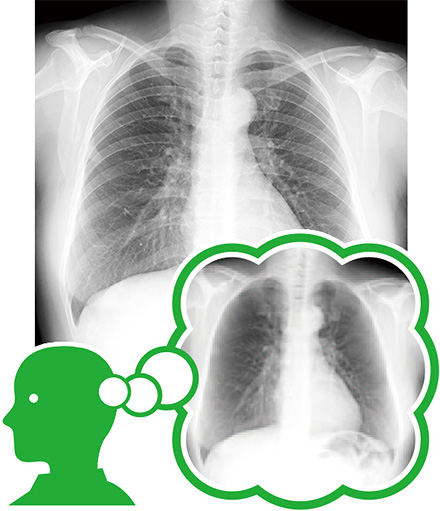

先生の頭の中のイメージを可視化する

「Bone Suppression処理」

1枚読影の胸部単純X線画像を見ると、肺野の約75%に鎖骨と肋骨がオーバーラップしています。

隠れた場所の病変を見逃さないため、先生方は、頭の中で鎖骨と肋骨を除いてイメージし、読影を行います。

それを可視化する画像技術が「Bone Suppression(ボーン・サプレッション)処理」です。

コニカミノルタのBone Suppression処理は、独自の胸部X線画像データベースをもとに、高度なアルゴリズムで鎖骨と肋骨のみを減弱します。

また、鎖骨と肋骨が写っている「オリジナル画像」と「 Bone Suppression処理画像」の切り替え表示が可能ですので、視点を変えることなく、骨の有無の状態がわかり、残像効果により病変を判別しやすくなっています。